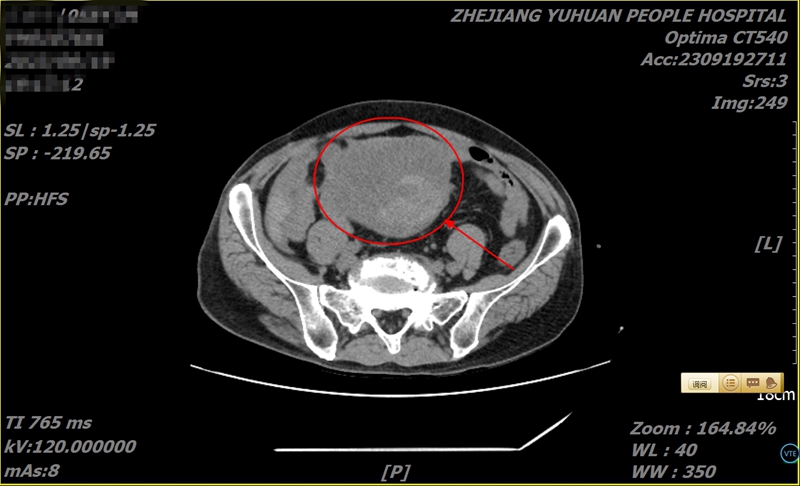

果不其然,杨叔一来到玉环市人民医院,外科副主任医师张富火速为其检查,竟发现小肠上有一橄榄球大小的巨型肿瘤,且伴有肠梗阻,盆腔积液、积血!

“赶紧通知手术室急诊手术!”张富凭借经验判断,这是罕见的小肠间质瘤,且已经破裂出血,手术时间不容延误。

危急时刻,完善术前准备后,杨叔转瞬被送往手术间,张富与医生周方建二人紧急为其手术。术中发现,肿瘤最长直径长达12厘米,瘤体上方一血管破裂,腹腔积血已达250毫升。

最终历时2小时,张富与周方建默契配合,成功摘除巨型肿瘤,杨叔转危为安。最后病理切片证实,确为胃肠间质瘤。